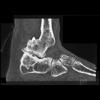

Radiographic findings on CT (Figure: OA of the foot) are the same as those detected by conventional radiographs, including subchondral sclerosis, asymmetric or nonuniform joint space narrowing, osteophytes, subchondral cysts, and in some cases osteocartilaginous intrarticular fragments. In addition, plantar and posterior calcaneal spurs are manifestations of degenerative joint disease; although, they are often asymptomatic.